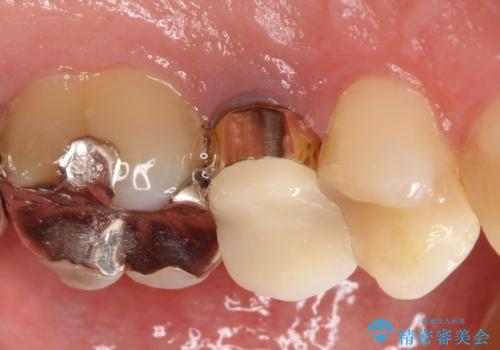

- 左上の後ろから3番目の歯のかぶせ物が適合不良であったので、根管治療を行い、オールセラミックを装着する計画としました。

またその隣の目立つ銀歯も同時に、セラミックに交換することとしました。

根管治療からかぶせ物まで精度の高い治療をおこないました。